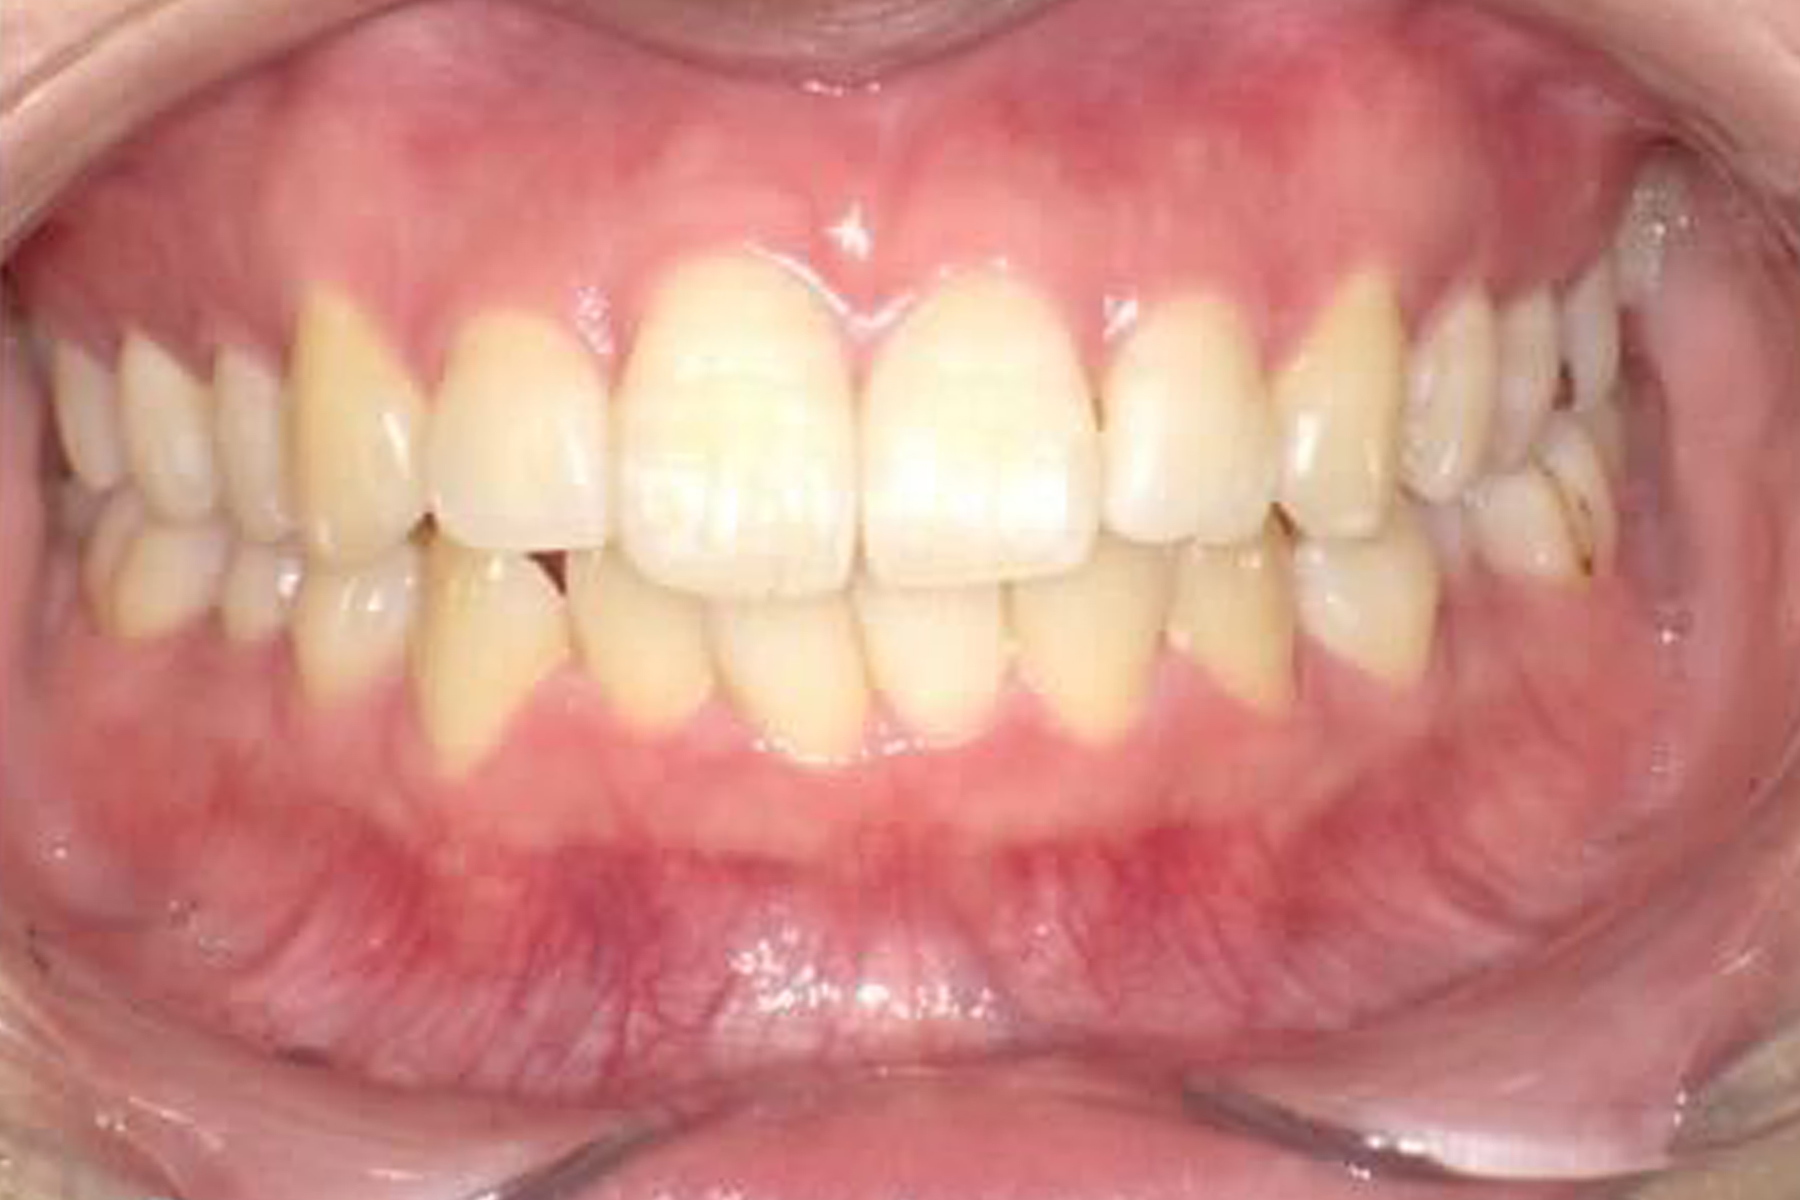

Case.1

BEFORE

AFTER

| 担当医 | 林 大貴 |

|---|---|

| 主訴 | 歯並びを直したい |

| 期間 | 約6ヶ月 |

| 費用 | 550,000円 |

| 治療内容 | マウスピース矯正 |

| 治療に伴うリスク | 動的治療後、保定装置を決められた期間確実に装着しなかったり した場合後戻りが起こる可能性があります。 |